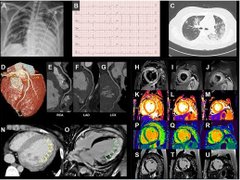

Ca bệnh điển hình chứng tỏ ngoài phổi, COVID-19 còn tổn hại tới tim

Hàn Quốc công bố một bệnh nhân mắc COVID-19 đầu tiên có phát bệnh về tim vào cuối tuần qua. Thông tin cho thấy virus SARS-CoV-2 thường gây bệnh liên quan tới hô hấp có thể có các triệu chứng phức tạp ở diện rộng hơn.